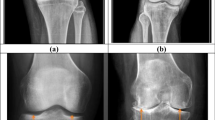

Joint effusion, or accumulation of fluid, is commonly seen in OA patients19. This feature of OA has been associated with increased levels of pain20 and risk of cartilage loss21, demonstrating the importance of accurate assessment of effusion in OA patients. Although the composition of effusion is not well understood, its severity is correlated with the inflammation present and graded as mild, moderate, or severe. While there are multiple methodologies for quantitatively assessing effusion severity19, one commonly used metric is the MRI Osteoarthritis Knee Score (MOAKS) effusion-synovitis score22. This metric takes into account the fluid equivalent signal within the joint cavity on images with T2-, intermediate-, or proton-density-weighted contrast including synovitis and effusion and therefore uses the term effusion-synovitis, and will be referred to as MOAKS-ES in this work for brevity. This is scored on a scale of 0–3, with 0 being a physiologic amount, 1 being small (fluid continuous in the retropatellar space), 2 being medium (with slight convexity of the suprapatellar bursa), and 3 being large (with evidence of capsular distention). Examples of sagittal TSE images with each of these grades are shown in Fig. 1. This methodology has been used in several studies, including using data from the Osteoarthritis Initiative (OAI), a large multi-center study evaluating close to 5,000 OA patients23,24. However, this assessment often requires manual evaluation by a radiologist of a high-resolution image in the axial plane, which can become a laborious process for large patient volumes. Furthermore, such assessment can result in substantial inter- and intra-rater disagreements22. Additionally, several benefits would result from enabling effusion grading based on low-resolution images. A lower-resolution scan, employing fewer phase encodes, would shorten the scan, improving the patient experience and potentially increasing scanner throughput. Low-resolution processing also has value when using low-field MRI devices. This technique has seen substantial development in recent years and allows low-cost medical imaging in settings not applicable for conventional scanners, but typically acquires lower-resolution data25,26,27,28,29. There is therefore an unmet need for automating effusion estimation from MR images, including from images acquired non-axially with a low resolution.

Examples of subjects with (a) Normal knee (MOAKS score 0), (b) Small effusion (MOAKS score 1), (c) Medium effusion (MOAKS score 2), and (d) Large (MOAKS score 3) effusion. In this work, a binary classification is used, with images as in panel (a) classified as without effusion, while images as in panels (b–d) are classified as with effusion.